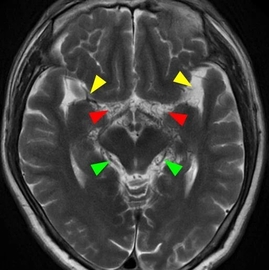

• 心脏磁共振在肝豆状核变性心肌损害中的研究进展